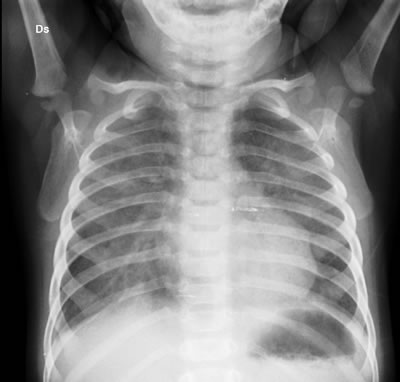

Il quadro che ci appare (Figura 1) è quello di un polmone “sporco” come da polmonite interstiziale.

Il sospetto è che il bambino possa avere una polmonite interstiziale o da virus o da Pneumocisti carinii. La diagnosi di polmonite da Pneumocisti carinii viene confermata il giorno seguente dalla ricerca biologica su aspirato (PCR positiva). Gli esami avviati per la ricerca di altri possibili agenti eziologici di polmonite interstiziale in immunodepresso (CMV, virus parainfluenzali) arriveranno nei giorni seguenti, e sono negativi.

Le condizioni cliniche del piccolo peggiorano rapidamente "sotto i nostri occhi"; nel corso della serata la saturazione scende (SaO2 72%) e si rende necessario il supporto con ossigeno in nasocannule (4 L/min). Il giorno seguente le condizioni non migliorano, ed a 48 h circa dall’inizio della terapia il piccolo è trasferito in terapia intensiva per essere intubato ed eseguire ventilazione meccanica (VM). Il quadro radiologico toracico si rende più evidente (Figura 2). Necessita di VM per 5 giorni, poi migliora progressivamente fino alla guarigione. È in attesa del trapianto del midollo.

L’esecuzione di una lastra del torace può mettere in luce il quadro di polmonite interstiziale caratteristico, prima che la malattia si renda clinicamente più evidente, e suggerendo da subito il trattamento antibiotico adeguato.

C’è un aspetto caratteristico dell’RX torace?

Inizialmente l’RX può essere normale (come nel nostro caso). In seguito possono comparire infiltrati interstiziali peri-ilari, con progressione verso la periferia. Il quadro può progredire con consolidamento degli spazi aerei (alveolari) bilaterali, mimando un edema polmonare, ma con risparmio degli spazi costo-frenici e degli apici.